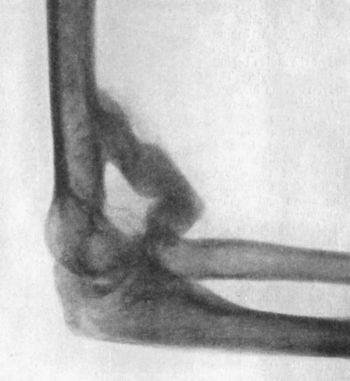

39.Forward Dislocation of Elbow, with Fracture of Olecranon93

40.Radiogram of Forward Dislocation of Head of Radius, with Fracture of Shaft of Ulna95